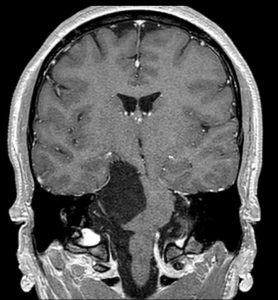

Διενεργήθη οπισθοσιγμοειδική οστεοπλαστική προσπέλαση και ολική εξαίρεση της βλάβης.

Η μετεγχειρητική αξονική τομογραφία εγκεφάλου δείχνει πλήρη αφαίρεση της βλάβης. Η ιστολογική εξέταση ανέδειξε επιδερμοειδή κύστη (Epidermoid Cyst, WHO Grade I)